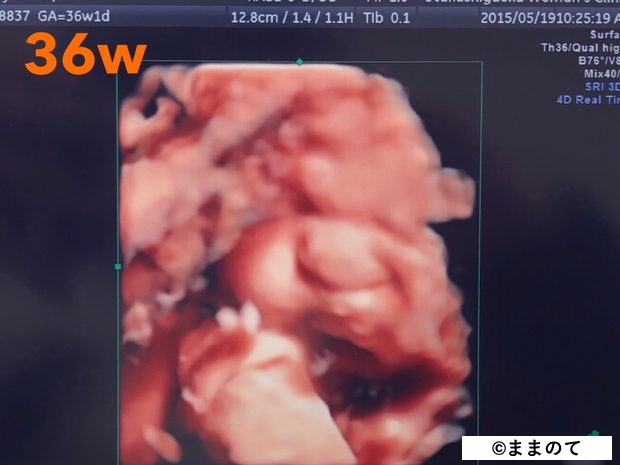

妊娠10ヶ月(36・37・38・39週)

臨月となり、赤ちゃんはいつ生まれてもおかしくない身体に成長しています。エコー写真には存在感のある顔が写ることもありますよ。

身長は約50cm、体重は3,000gが目安ですが、赤ちゃんの成長には個人差があるため、医師から特別な指導がなければ安心して赤ちゃんと対面できるときを待ちましょう。